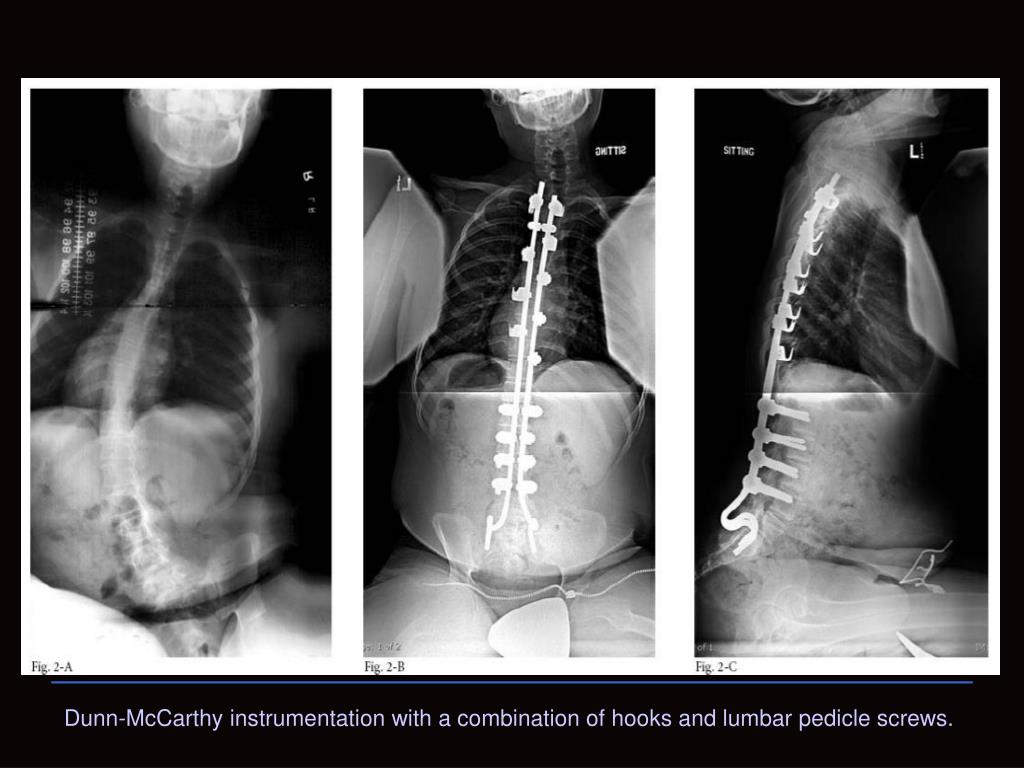

21. Dunn-McCarthy instrumentation with a combination of hooks and lumbar pedicle screws.